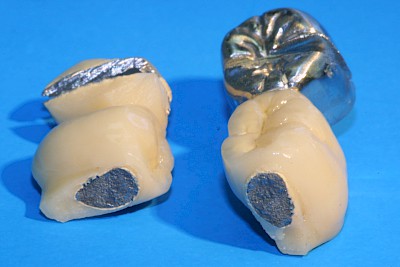

Krone: Randspalt

Randspalten bzw. Defekte im Randbereich sind immer auch verdächtig für Karies.